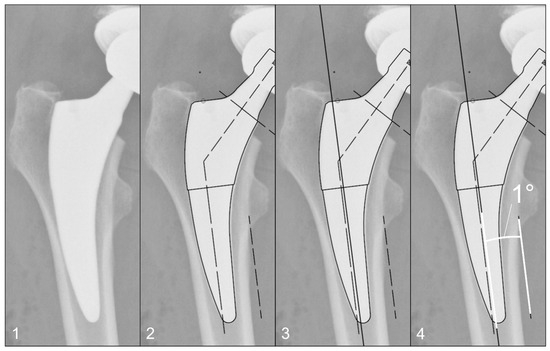

The radiographs were analysed with TraumaCad® software (Brainlab AG, Munich, Germany). We used only standardised deep-centered anteroposterior X-rays of the pelvis, with the central beam perpendicular to the midline and centered over the symphysis, and the legs positioned in 15° of internal rotation with the patient in the supine position. The images were calibrated by measuring the length of the depicted stem from its shoulder to its tip and equating it with the corresponding planning template. In this way, we could avoid any possible errors in our established calibration method with a reference sphere, which can be placed too far away from the central beam or too far away from the film. The measurements of the stem position were subsequently taken on the same axis to neutralise distortions caused by varying flexion and rotation positions of the leg during radiography (Figure 2). The varus/valgus alignment of the stems was determined by measuring the angle between the longitudinal axis of the stem and the longitudinal axis of the femoral canal (Figure 3). Subsidence was determined by measuring the distance from the shoulder of the stem to a clearly definable point at the greater trochanter in the previously determined longitudinal axis of the stem (Figure 4). Due to possible osseous changes over time, such as enthesiopathies or ossifications at the tip of the greater trochanter, defining this point was crucial to measure the correct distance.

Figure 4. Method for measuring the stem position: (1) Identification of a clearly definable point on the greater trochanter, which appears identically on all radiographs up to 10 years postoperatively. (2) Calibration of the image using a planning template, as shown in Figure 2. (3) Determination of the femoral longitudinal axis. (4) Distance measurement of the defined point to the prosthetic shoulder along the femoral longitudinal axis.